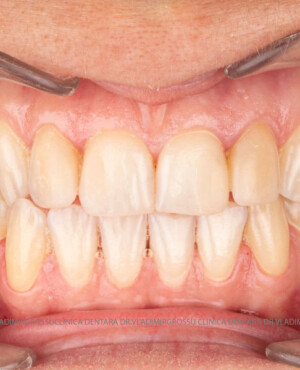

Cazuri clinice

Caz 2

Restaurări cu coroane din zirconiu vs fațete ceramice

Transformările estetice și impactul reabilitării asupra vieții pacienților

Reabilitarea dentară produce o schimbare vizibilă și profundă în aspectul pacientului, cu efecte pozitive evidente asupra stimei de sine și a calității vieții. Mulți pacienți relatează bucuria redobândirii funcției masticatorii și dispariția complexelor legate de aspectul dentar.